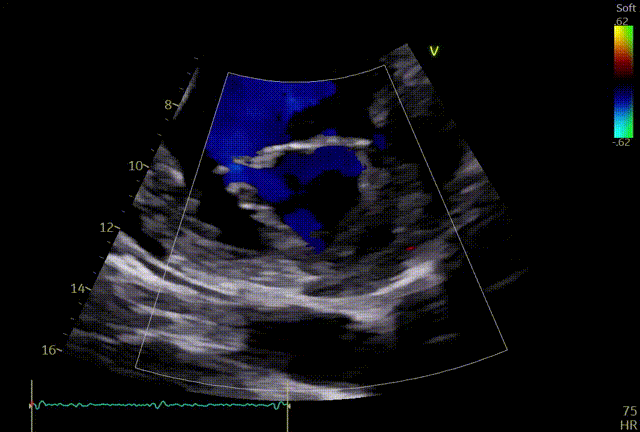

第一个夹子XTW

关小夹子,进入到左室后,跨瓣越过瓣叶尖端后,立马打开夹子,三维再次确认夹臂方向未改变,慢慢往上提拉,一次准确捕获瓣叶,前后叶Bouncing明显,后叶接近根部,关紧夹臂,反流量整体减少,但是内外侧都残余反流,内侧为主。反流明显减少,后叶夹持10mm以上,夹子稳定性良好,跨瓣压差小于3mmHg,决定释放。

释放前评估

释放后